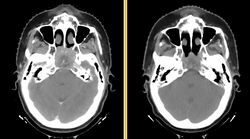

RT structure set and RT dose overlayed onto CT

DICOM-RT is an open standard exchange format for radiotherapy objects. It is well established, and is supported by nearly every modern commercial software product. The DICOM-RT data set comprises four objects: RT Dose, RT Plan, RT Structure Set, and RT Image. Briefly, RT Plan specifies the treatment beams, including beam angles, beam sizes and apertures, couch angles, and radiation output. The RT Plan is associated with a CT image through the use of the DICOM UID mechanism. An RT Dose is the output of a dose computation, measured in Gray, and is similarly associated with both a CT image and an RT Plan. The RT Structure Set contains annotations of a CT image, either points or contours, and contains the geometric boundaries of organs and structures of interest. It is associated with a CT image. Finally, the RT Image is primarily used for 2D images used in patient positioning.

Our project goal for data interchange is to provide import and export capabilities for RT Dose and RT Structure Set in the NA-MIC kit. These two DICOM items form the minimal set necessary to implement adaptive radiotherapy. Beam isocenter information is stored in the RT Plan, so we will provide RT Plan import capability as a part of plan review. RT Plan export and RT Image are outside of the scope of this project.